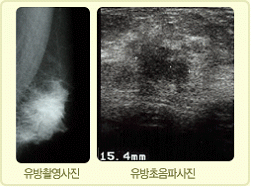

2) À¯¹æÃÔ¿µ¼ú

À¯¹æÀÇ ¾ç¿·¸é°ú »óÇϸ¦ ´©¸¥ÈÄ X-ray·Î ÃÔ¿µÇÏ¿© ¿µ»óÀ» ¾ò´Â ¹æ¹ýÀ¸·Î ¹æ»ç¼± ±â»ç¿¡ ÀÇÇØ ´ë·®À¸·Î ÃÔ¿µÀÌ °¡´ÉÇÑ ¹Ý¸é¿¡ À¯¹æÀÇ ÀÛÀº ¸Û¿ïÀº Àß ¾È³ªÅ¸³ª´Â ¼ö°¡ ÀÖ½À´Ï´Ù.

3) À¯¹æ ÃÊÀ½ÆÄ °Ë»ç

2~3mm Å©±âÀÇ ¾ÆÁÖ ÀÛÀº Á¾±«µµ ã¾Æ³¾ Á¤µµ·Î È¿À²ÀûÀ̳ª °Ë»ç ½Ã°£ÀÌ ¸¹ÀÌ ¼Ò¿äµÇ°í ½Ã¼úÀÚ¿¡ µû¶ó °á°ú ÆÇµ¶ÀÇ Á¤È®¼º¿¡ ¸¹Àº Â÷À̰¡ ÀÖÀ¸¹Ç·Î °æÇè ¸¹Àº À¯¹æ Àü¹®Àǻ翡 ÀÇÇØ¼­ ½ÃÇàµÇ¾î¾ß¸¸ Á¤È®ÇÑ Áø´ÜÀ» ³»¸± ¼ö ÀÖ½À´Ï´Ù.